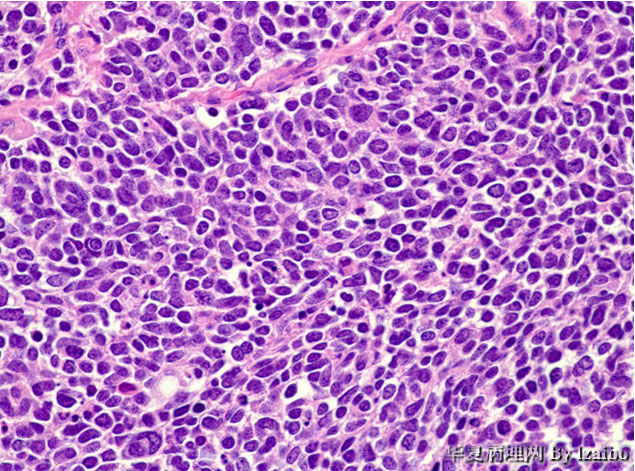

51岁女性表现为慢性疲劳和虚弱持续约6个月。 CT扫描显示左肾脏巨大肿块。病人接受根治性肾切除术。

大体标本描述:肿块位于左肾上极,大小为15×9×8.5厘米。切面上,肿瘤为黄色,并具有散落的白色区域和偶尔出血区,没有明显坏死区。肿瘤非常接近血管,但大体上没有侵入到血管壁。大体上可见肿瘤侵犯输尿管和骨盆(图1和图2)。显微图片(图3-7)。

• 病例1-摘自UPMC Web Cases图3

图3

• 病例1-摘自UPMC Web Cases图4

图4

• 病例1-摘自UPMC Web Cases图5

图5

• 病例1-摘自UPMC Web Cases图6

图6

• 病例1-摘自UPMC Web Cases图7

图7

镜下 肿瘤细胞成巢片状分布,成浸润性生长,侵及神经组织,瘤细胞体积较小,细胞形态呈圆形,椭圆形,短梭形 ,多 角形,核染色质较细腻,核仁不明显,有的隐约可见,胞浆极少。偶就少量的红色胞浆5图,分裂像可见。

诊断 :(左肾上极) PNET.

诊断:肾神经内分泌癌。

跟在其他解剖部位的神经内分泌肿瘤一样,肾神经内分泌肿瘤可以有不同程度的神经内分泌分化[类癌,非典型类癌,小细胞癌(SCC),大细胞神经内分泌癌(LCNEC)]。肾类癌最常见,为低级别神经内分泌肿瘤,但临床可呈现进展性过程。跟其他解剖部位相似,肾脏小细胞癌和大细胞神经内分泌癌为高度侵略性,远处转移常见,预后极差。

肾类癌和小细胞癌各有自己的组织学特征,病例医生可基于形态学作出准确诊断。神经内分泌分化标记物的免疫染色可用来确认诊断。Synaptophysin是最敏感的神经内分泌分化标记物。也可用其他神经内分泌分化标记物如chromogranin和CD56,但较不敏感。 跟其他神经内分泌肿瘤相比, 大细胞神经内分泌癌较难以诊断,易与高级别肾细胞癌或尿道上皮癌混淆。意识到大细胞神经内分泌癌可发生于肾脏和认真取材可避免误诊。神经内分泌分化标记物的阳性免疫染色和CD10的阴性免疫染色倾向大细胞神经内分泌癌的诊断。